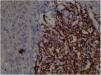

Immunohistochemistry: TCD4 diffuse positivity in 80% of lymphocytic infiltrate cells, focal positivity of 40% TCD3 cells, diffuse myeloperoxidase positivity in more than 90% of cells, TCD8 positivity in about 30% of cells, CD79a positivity in rare lymphoid cells of the dermis, Ki67 positivity in about 30% of the cells. 40× magnification.

A 57-year-old female patient, Caucasian, with a previous diagnosis of hypertension, using losartan, and with acute myeloid leukemia for one year. She underwent chemotherapy with daunorubicin for three months and was in maintenance with transretinic acid 70mg at the time of the consultation. She sought the dermatology service because of painful and itchy lesions on the scalp, which had arisen 20 days before and were preceded by local burning (Fig. 1). The proposed diagnostic hypotheses were cutaneous metastasis, cutaneous T-cell lymphoma, and pharmacodermia. An anatomopathological examination was performed, which demonstrated a dense diffuse infiltration of lymphocytic cells, atypical and large cells, four-to-five times the usual size of mature lymphocytes, with bizarre formats and convoluted nuclei in the superficial, intermediate, and deep dermis, with extension to the hypodermis, sparing the epidermis (Fig. 2). Immunohistochemical study of the lesion revealed diffuse positivity for CD43 in 80% of cell infiltrate, diffuse positivity for myeloperoxidase in more than 90% of cells, Ki67 positivity in about 30% of cells, and granzyme, alk1, CD3, CD20, and CD30 negativity (Fig. 3). Therefore, the diagnosis of myeloid sarcoma was established. At the end of the chemotherapy, she presented total remission of the hematological alterations; however, as she maintained lesions on the scalp, retreatment with radiotherapy was utilized. However, the lesions remained unchanged and the patient evolved with relapse of myeloid leukemia, with a new chemotherapy protocol initiated by the hematology team.